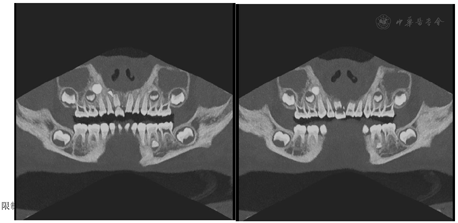

点击查看大图

图3

CT CPR重建图 显示右侧中切牙中间断裂